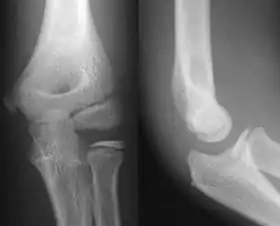

- آرنج - AP و جانبی. تصاویر موجود سر استخوان رادیوس در صورت درخواست.

پروجکشن جانبی

پروجکشن قدامی خلفی

پروجکشن مایل داخلی ۳۰ درجه آرنج چپ

پروجکشن مایل خارجی ۳۰ درجه آرنج چپ